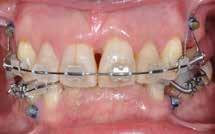

Objektivt anbefales behandling af det dybe bid, som ubehandlet forventes at forværres yderligere over tid. Patienten har ønske om behandling med æstetisk ortodontisk apparatur, alignere, og det vurderes muligt at behandle malokklusionen med alignere. Dog anbefales det generelt, at alignere undgås eller benyttes med væsentlige modifikationer af alignerens retention ved tandmobilitet, da dette ellers kan medføre jiggling, når aligneren tages af og på mange gange dagligt. På den anden side er der nogen evidens for, at alignerbehandling er associeret med bedre renhold og parodontal sundhed sammenlignet med fast apparatur (16).

Der planlægges alignerbehandling af begge kæber med intrusion af 1+1 og 2,1-1,2, nivellering af trangstilling UK med interproksimal reduktion (IPR) (Fig. 2 A, B) og senere IPR OK for reduktion af dark triangles mellem incisiverne efter nivellering. Patienten instrueres i at benytte alignere 20-22 timer/ dag med alignerskift hver 7. dag, og patienten ses hver 3.-8. uge under forløbet. Den første alignerserie består af 16 alignere for nivellering OK/UK og IPR i UK (Fig. 2). Efter denne serie planlægges IPR mellem incisiverne i OK for reduktion af dark triangles (Fig. 3) samt yderligere intrusion af OK og UK-fronten i 12 refinement-alignere. Patienten udviser god kooperation og er meget tilfreds med alignerapparaturet, som er mindre synligt end det faste apparatur (Fig. 4).

Behandlingen afsluttes med yderligere refinement-alignere for finindstilling af okklusionen, og efter 11 måneders ortodontisk behandling er der opnået normale relationer i alle tre